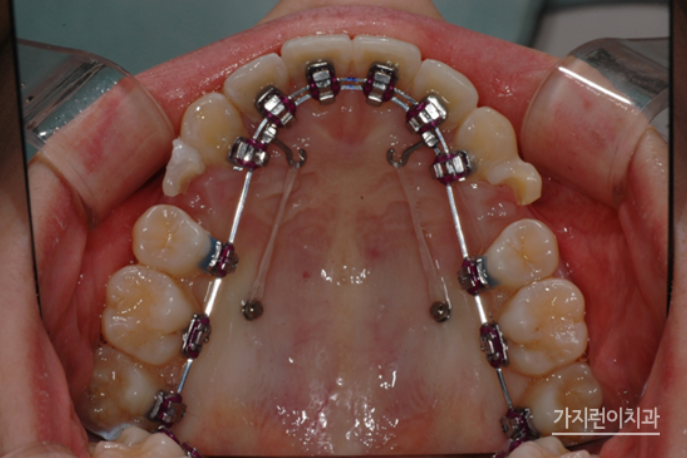

더블와이어 설측탄댐장치란!?

위 사진은 더블와이어를 이용한 설측탄댐장치인데요. 치아의 비뚤어짐이나 쓰러짐, 뿌리 조절 등을 정교하게 컨트롤할 수 있는 교정장치입니다. 3차원적인 치아이동 조절을 위해 특수하게 고안된 장치인데요. 기존의 설측교정장치가 뿌리 이동이 용이하지 않았다는 단점을 개선해 미세한 조절이 가능해졌다는 특징이 있습니다.